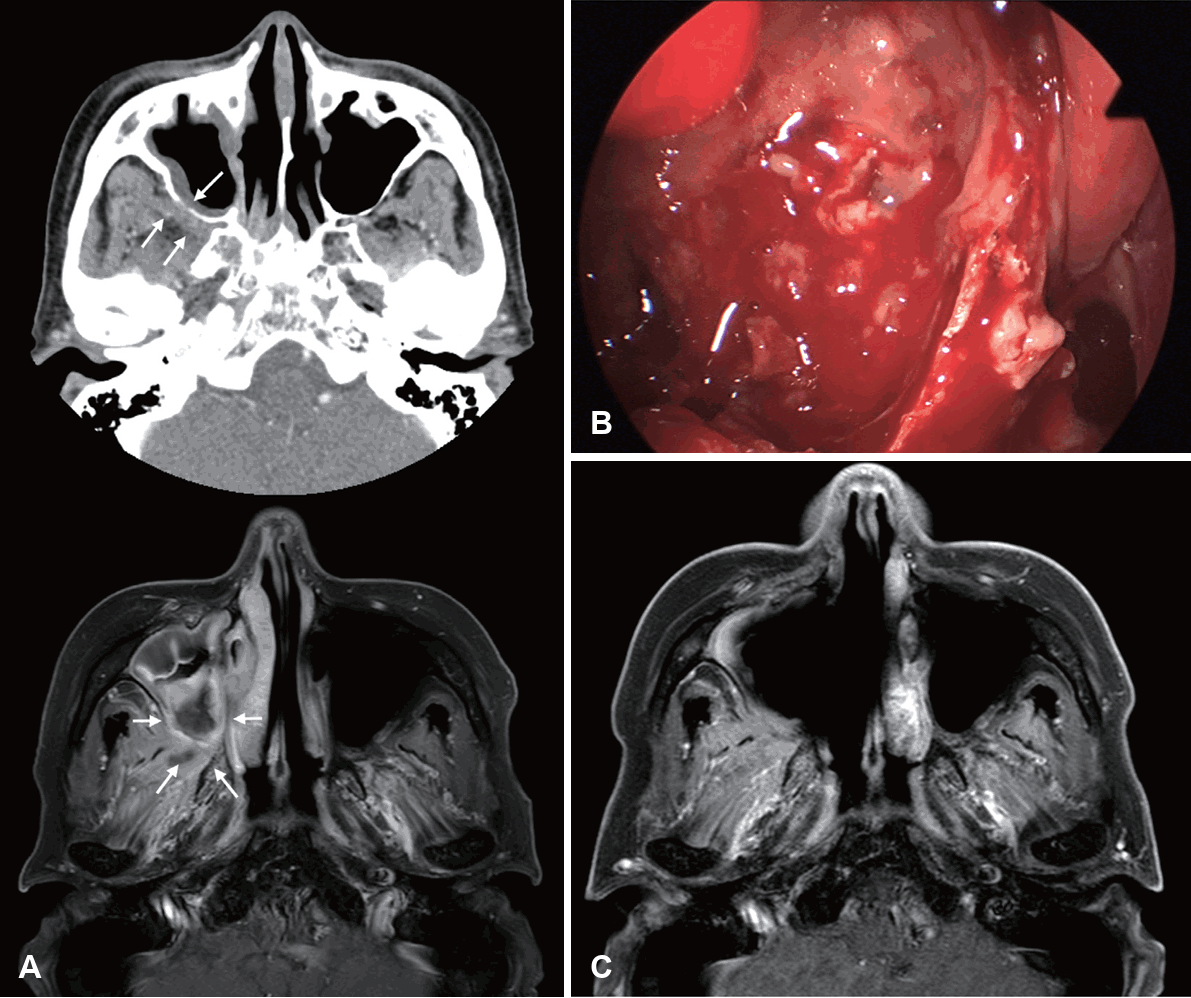

Image findings of CIFRS and CGIFRS are distinguished from those of AIFRS. CIFRS showed diffuse infiltrative patterns, whereas CGIFRS showed mass-forming patterns. The infiltrative pattern of CIFRS is characterized by a more extensive combined inflammation without focal mass formation (Fig. 3) [17]. The mass-forming pattern of CGIFRS is challenging to differentiate from malignancy (Fig. 4) [57,58]. On MRI, the T2 signal intensity of lesions of CIFRS was mainly intermediate (25%) to high (66%), whereas 50% of lesions of CGIFRS had low T2 signal intensity. Low T2 signal intensity is known to be associated with the presence of paramagnetic elements, such as iron and magnesium, or with hyphae [58,59]. Differences in inflammatory processes between CIFRS and CGIFRS may lead to differences in their radiologic features [17]. Other imaging features of CIFRS and CGIFRS are both bony sclerosis and bony erosion, with more than half showing tissue necrosis [17,60]. Sclerotic changes in bone are characteristic of a chronic course of sinusitis or underlying combined chronic sinusitis. In contrast, bony erosion and tissue necrosis may be indicators of the invasiveness of sinusitis [58,60]. Although these imaging findings may be important, they are not observed in all patients with CIFRS and CGIFRS and are therefore not diagnostic [17].

MR images and intraoperative finding of a patient with chronic granulomatous invasive fungal sinusitis. A: CT scan revealed bony destruction in the anterior wall of the left maxillary sinus and an irregular enhancing soft tissue lesion extending into the left maxillary sinus, cheek, infraorbital canal, and superior orbital wall (white arrow). These findings suggested chronic invasive fungal sinusitis vs. malignancy in the left maxillary sinus. MR images reveal an irregular T2 low signal intensity soft tissue lesion in the left maxillary sinus and its anterior and posterolateral walls. There is bony destruction extending to the left cheek (white arrow) and retroantral fat area. Irregular central T2 low signal intensity lesion within maxillary sinus (yellow arrow) shows calcific density on CT, suggesting fungus ball. The findings indicated that chronic invasive fungal sinusitis is more probable than a neoplastic condition in the left maxillary sinus. B: The anterior wall of the maxilla and infraorbital nerve were necrotic and completely resected via Caldwell-Luc operation. C: Postoperative gadolinium-enhanced MR image showed no remnant LoCE lesions.